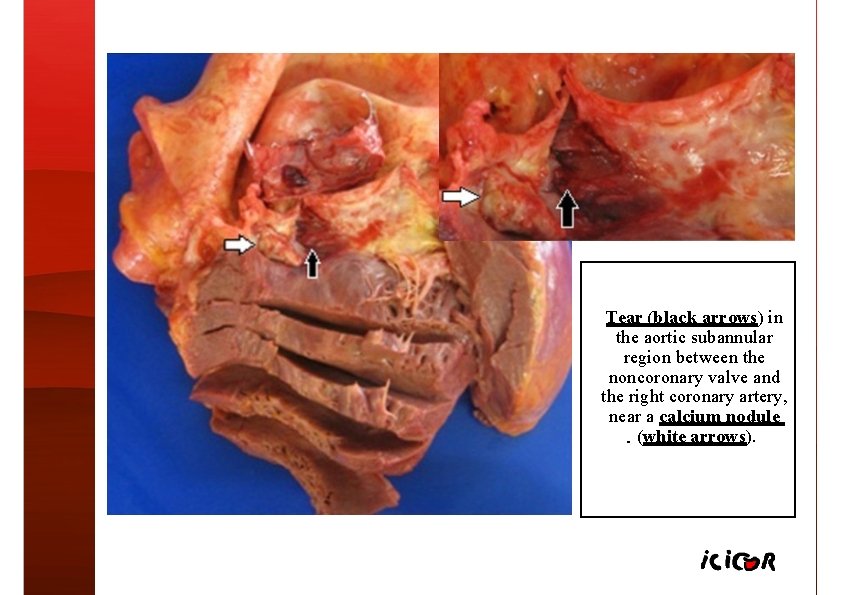

Tear (black arrows) in the aortic subannular region between the noncoronary valve and the right coronary artery, near a calcium nodule (white arrows).